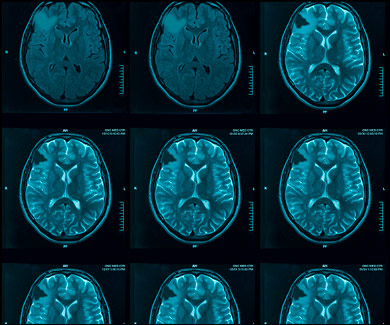

What is VORANIGO?

VORANIGO (40 mg tablets) is a prescription medicine used to treat adults and children 12 years of age and older with certain types of brain tumors called astrocytoma or oligodendroglioma with an isocitrate dehydrogenase-1 (IDH1) or isocitrate dehydrogenase-2 (IDH2) mutation, following surgery. Your healthcare provider will perform a test to make sure that VORANIGO is right for you. It is not known if VORANIGO is safe and effective in children under 12 years of age.